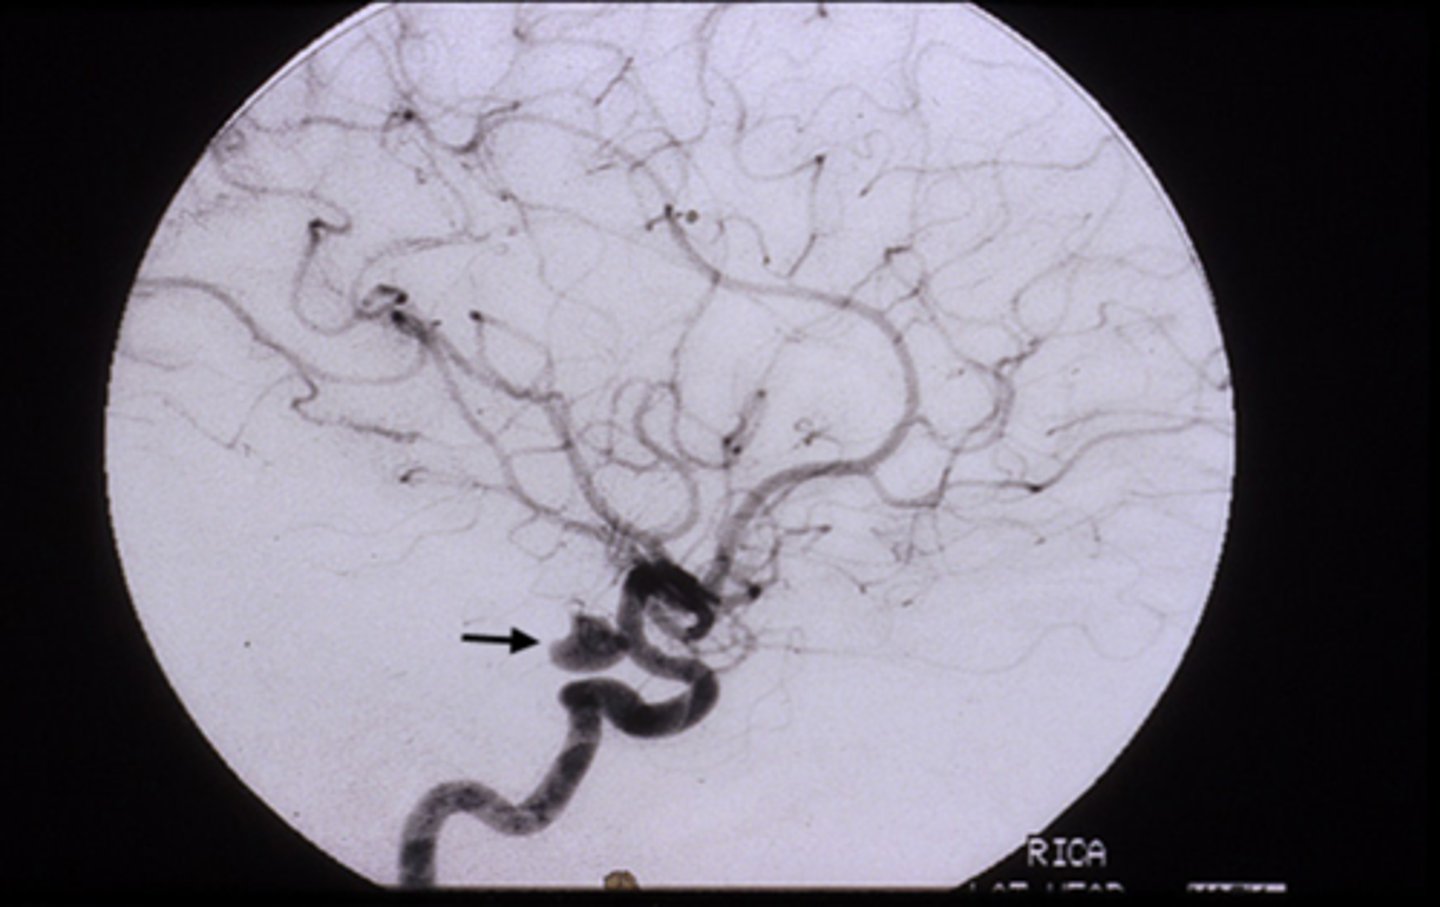

fixed, dilated pupil (esp if painful like HA) = anuerysm at the junction of the ICA and posterior communicating artery

Explain the anatomy of the pupillomotor vs EOM fibers in the CN III.

pupillomotor fibers travel around the circumference of CN III

EOM fibers travel within the core of CN III

Why are most pupil-spared CN III palsies the result of DM or vascular etiologies?

vasa nervorum occlusion = infarcation of these small BV = focal areas of demyelination in the nerve core, while the outer pupillomotor fibers are spared

Explain how the Uncal region can affect CN III in Uncal syndrome.

CN III leaves brainstem = pupillomotor fibers move dorsomedially = uncus herniates = compresses CN III dorsomedially against petroclinoid ligament and dorsum sellae = pupil is blown